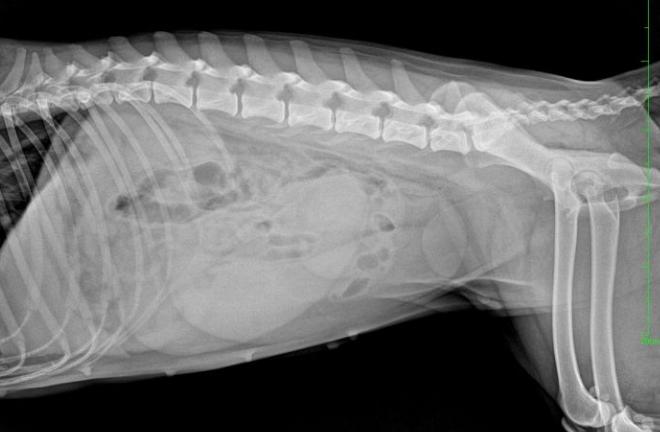

从外观上看,闭锁型子宫蓄脓因为脓液无法流出,势必会出现腰腹围增大,同时因为压迫心肺等脏器,多会引发宠物呼吸及心跳加速,严重的可引发呼吸困难。用手摸腹部,一般腹部紧绷,此时宠物喜卧,同时仍伴有精神不振,嗜睡,多饮多尿的情况发生。

触诊:医生可以在腹腔触诊的时候摸到很大的子宫,但如果是开放型的子宫蓄脓,通常子宫不会太大。仔细的进行腹部触诊,可以大约了解子宫的大小。不过动作不能太粗鲁,因为可能会将子宫弄破。

影像学诊断:因为胚胎45天内,在X光影像下并不明显,相对的,对于是否为怀孕或是子宫蓄脓就不容易早期诊断,此时腹腔超音波就有早期诊断的优势,因为胚胎成长24天后就可以藉由超音波来诊断,相对的,也可以更早区分怀孕(怀孕24天以后)与子宫蓄脓。